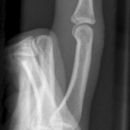

Grundgliedköpfchenfraktur